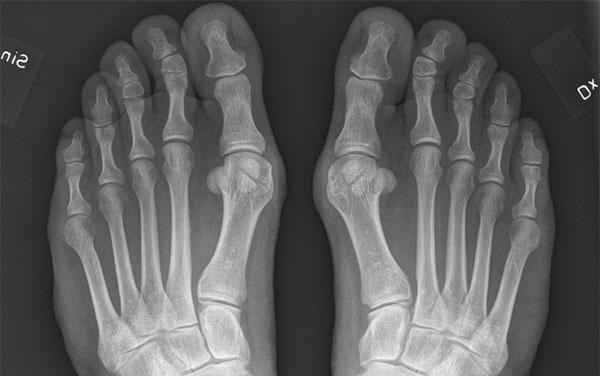

PLATT FOT BOT

Bakgrund: Platt Fot Bot eller HyProCure (Hyper pronation cure) är en metod som innebär att en titanskruv (stent) skruvas in i sinus tarsi på patienter med pes plonovalgus.

vid plattfot (se bild ovan). Genom att välja storlek på skruv kan man enkelt bestämma hur mycket fotvalv man vill ha. Metoden anges inte bara bota plattfot utan även besvär från höft, knä och rygg!

Resultat: Metoden marknadsförs intensivt på nätet och med hjälp av s.k. influencers. Trots att filosofin bakom metoden är biomekaniskt och biologiskt felaktig och trots att det helt saknas vetenskaplig dokumentation (om man undantar sju publikationer av metodens uppfinnare, varav flertalet avser försök på avlidna) har metoden fått viss spridning även i Sverige. Det finns ingen oberoende vetenskaplig granskning och inga långtidsuppföljningar. Däremot finns missnöjda patienter som inte bara fått skruvar inskruvade utan ofta även utskruvade.

Hypotes: genom att göra en artroris (skruva in en titanskruv mellan talus och calcaneus) kan fotens längsgående fotvalv återställas